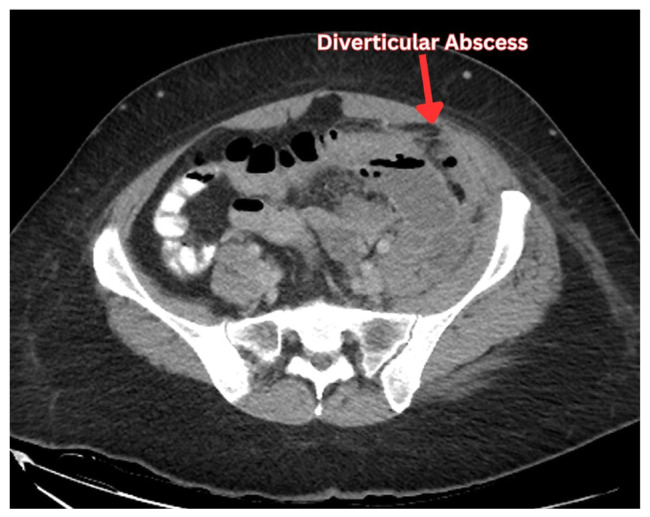

憩室囊的炎症称为急性憩室炎,有时可导致脓肿形成。经皮引流是治疗憩室脓肿的常规方法。作为一种用于从脓肿中清除大量感染液体的微创手术,经皮引流术成为一种有吸引力的选择。从历史上看,手术切除脓肿导致多次住院治疗,增加了医疗资源的负担。随着放射学技术的进步,ct引导下经皮引流憩室脓肿确保了患者满意度的提高和医疗成本的降低。选择手术或经皮引流憩室脓肿仍然是一个问题的争论医师。经皮引流手术的结果在文献中是分散的。在憩室脓肿的治疗过程中,熟悉经皮引流或结肠切除术的选择标准是很重要的。经皮引流可以防止紧急结肠切除术,但它并不总是一个无风险的程序。可引起持续性脓肿、新发脓肿、腹壁脓肿、腹膜炎等并发症。因此,医生必须提前做好准备,通过选择合适的人群进行手术,并确保良好的导管护理,包括重新调整导管,冲洗导管和升级导管尺寸,以预防这些并发症。医生不仅要预防这些并发症,还要有效地治疗它们。本文旨在从临床角度总结经皮引流憩室脓肿的重要结果及其进一步处理。

The inflammation of the diverticular pouch is called acute diverticulitis which can result in abscess formations sometimes. Percutaneous drainage is routinely considered for the management of diverticular abscesses. Being a minimally invasive procedure employed for the removal of large collections of infected fluid from the abscesses, percutaneous drainage emerged as an appealing option. Historically, surgical removal of the abscesses has resulted in multiple hospitalizations and an increased burden on healthcare resources. With the advancement in radiological techniques, CT-guided percutaneous drainage of diverticular abscesses ensured enhanced patient satisfaction and reduced healthcare costs. The choice between surgery or percutaneous drainage of diverticular abscess remains a matter of debate among physicians. The outcomes of percutaneous drainage procedures are scattered across the literature. It is important to be familiar with the criteria regarding the choice of percutaneous drainage or colectomy during the management of diverticular abscesses. Percutaneous drainage can prevent emergent colectomy but it is not always a risk-free procedure. It can bring complications including persistent abscess, new onset abscess, abdominal wall abscess, and peritonitis. Therefore, a physician must prepare in advance to prevent these complications by selecting the right population for the procedure and ensuring good catheter care which involves readjusting the catheter, flushing the catheter and upgrading the size of the catheter. A physician not only prevents these complications but also effectively treats them. This review paper aims to summarize the important outcomes of percutaneous drainage of diverticular abscesses and their further management from a clinical standpoint.